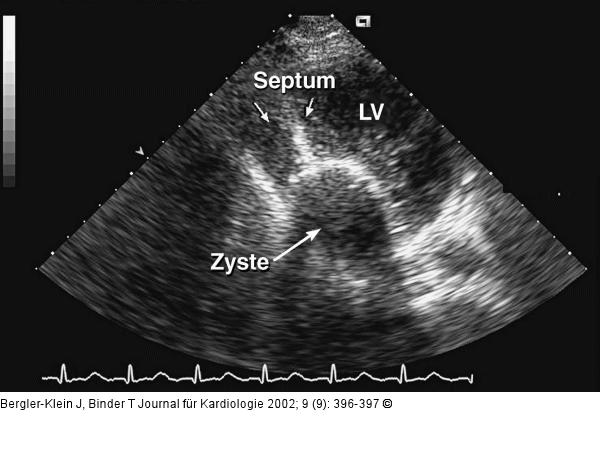

Abbildung 5: Intramyokardiale Echinokokkus-Zyste

Vorwölbung der ca. 6 cm x 4 cm großen Zyste in den linken Ventrikel. LV = linker Ventrikel. |